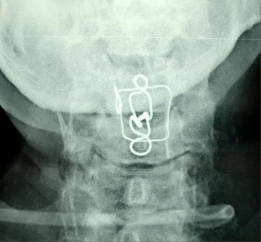

SAU MỔ (27 - 5 – 2008)

(Nắn vào tốt, cố định tốt)

HÌNH THẲNG HÌNH NGHIÊNG

MRI SAU MỔ: không thấy thoát vị đĩa đệm, nghi ngờ có phù nề tủy và chèn ép phía sau, do hình bị nhiễu nên không rõ.